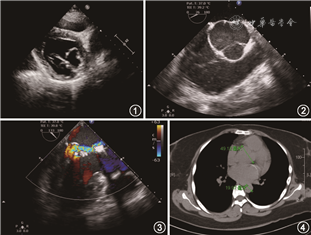

患者 女性,22岁,因“房间隔缺损修补+二尖瓣成形术后8年,活动后胸闷不适2个月余”于2020年4月11日至我院门诊就诊。8年前因“发现心脏杂音10余年”在外院就诊,诊断为二孔型房间隔缺损、二尖瓣前叶脱垂并重度关闭不全,于2013年4月3日行房间隔缺损补片修补+二尖瓣瓣环成形+双孔成形术。2013年5月6日外院超声心动图提示房间隔未见分流,二尖瓣关闭对合欠佳,轻度反流,左心房内径32 mm,左心室舒张末内径47 mm,射血分数54%,主动脉窦部内径32 mm。后定期随访,无不适主诉。近2个月患者自觉活动后胸闷、气促不适,无咳嗽、咳痰、胸痛、夜间不能平卧、端坐呼吸,否认发热史,双下肢未见水肿,遂至我院就诊。患者母亲33岁时猝死。体检:蜘蛛指,胸椎、腰椎侧弯,屈光不正-4.00 D,一般情况可,心前区可见陈旧性手术瘢痕,心尖部可及3/6级收缩期杂音。我院超声心动图提示为房间隔缺损修补术后,心房水平未见残余分流,二尖瓣成形术后呈双口状且后叶脱垂伴中重度二尖瓣反流,主动脉窦部明显增宽(48 mm),左心房内径37 mm,左心室内径51 mm,射血分数62%(图1~3)。胸部CT检查结果提示主动脉窦部增宽(图4)。入院诊断为马方综合征,房间隔缺损和二尖瓣成形术后,二尖瓣关闭不全,主动脉根部瘤,心功能(纽约心脏病协会分级)Ⅱ级。